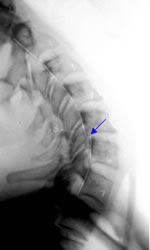

This extension x-ray image

illustrates ligamentous

instability at C5-C6.